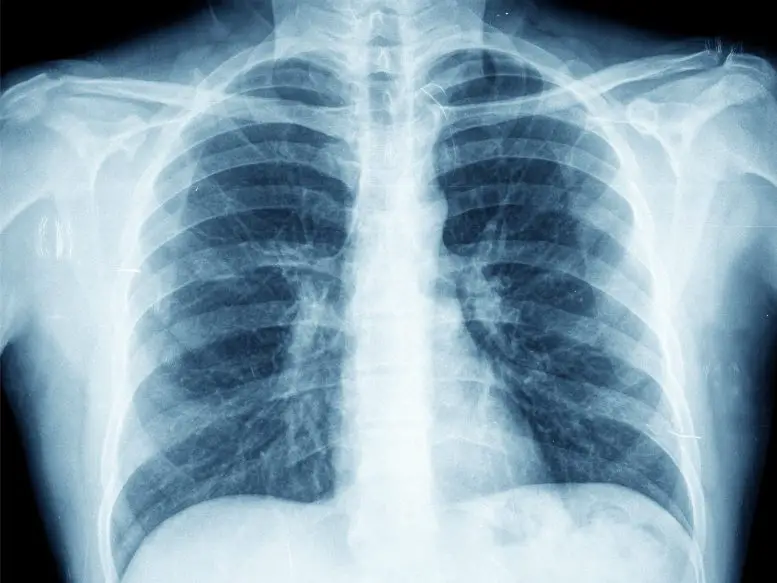

Рентгенологи превосходят искусственный интеллект в выявлении заболеваний легких по рентгеновским снимкам грудной клетки

В новаторском исследовании, опубликованном в журнале Radiology, рентгенологи превзошли искусственный интеллект (ИИ) в точности определения трех распространенных заболеваний легких по рентгеновским снимкам грудной клетки. В исследовании, проведенном группой ученых под руководством д-ра Луиса Л. Плеснера, врача-рентгенолога и доктора философии из больницы Херлев и Гентофте в Копенгагене (Дания), сравнивались результаты работы четырех коммерческих инструментов искусственного интеллекта и 72 врачей-рентгенологов при интерпретации более 2000 рентгеновских снимков грудной клетки.

Рентгенография грудной клетки является широко распространенным диагностическим инструментом в медицине. Однако для правильной интерпретации снимков требуется значительная подготовка и опыт. Хотя для помощи рентгенологам в постановке диагноза были разработаны средства искусственного интеллекта, их клиническое применение пока находится на ранней стадии. Д-р Плеснер подчеркивает необходимость дальнейшего тестирования инструментов ИИ в реальных клинических сценариях для определения их истинной диагностической точности.

В ходе исследования было проанализировано 2040 последовательных рентгеновских снимков грудной клетки взрослых, сделанных в течение двух лет в четырех датских больницах в 2020 году. Средний возраст пациентов составил 72 года, а на 32,8% рентгенограмм была выявлена хотя бы одна целевая находка, относящаяся к трем распространенным заболеваниям легких: патологии воздушного пространства, пневмотораксу и плевральному выпоту.

Результаты исследования показали, что рентгенологи превосходят инструменты искусственного интеллекта в точности определения наличия и отсутствия этих заболеваний легких. Хотя инструменты искусственного интеллекта были чувствительны к выявлению заболеваний, они также давали больше ложноположительных результатов, что делает их менее надежными для автономной диагностики. Однако инструменты искусственного интеллекта все же могут быть полезны для получения второго мнения, помогающего рентгенологам в их интерпретации.

Данное исследование подчеркивает превосходство рентгенологов над инструментами искусственного интеллекта в точности выявления распространенных заболеваний легких по рентгеновским снимкам грудной клетки. Хотя инструменты искусственного интеллекта продемонстрировали чувствительность в выявлении этих заболеваний, высокий процент ложноположительных результатов вызывает сомнения в их надежности для автономной диагностики.